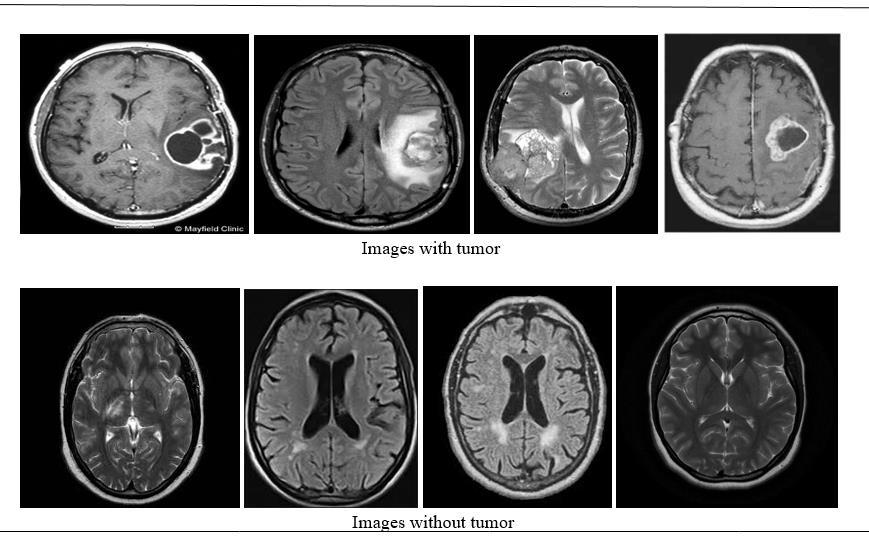

Abstract – Brain tumors pose significant challenges in medical diagnostics due to their complexity and the critical need for accurate and early detection. Machine learning (ML) has emerged as a powerful tool in medical imaging and diagnostics, offering the potential to improve the accuracy, speed, and reliability of brain tumor detection. Brain tumor detection is a critical aspect of medical diagnosis, as earlyand accurate identification of tumors significantly improves treatment outcomes and patient survival rates. However, traditional diagnostic methods,suchasmanualinterpretation of medical imaging, are time-consuming,subjective,andprone to variability. In recent years, machine learning (ML) has emerged as a transformative tool in medical imaging,offering automated, accurate, and scalable solutions for tumor detection. This review paper explores the advancements in machine learning techniquesappliedtobraintumordetection, focusing on methodologies, datasets, andclinicalapplications. We provide an overview of key algorithms, including supervised learning, unsupervised learning,anddeeplearning models, highlighting their roles in tumor segmentation, classification, and prediction. Special attention is given to convolutional neural networks (CNNs) and their efficiency in processing medical imaging modalities such as MRI. Finally, we examine the integration of ML-based systems into clinical workflows, emphasizing their potential to complement radiologists and improve patient outcomes. This review aims to serve as a comprehensive resource for researchers and clinicians interested in leveraging machine learning for brain tumor detection and treatment planning.

Traditionaldiagnosticmethods,suchasmanualanalysisof magnetic resonance imaging (MRI), are time-consuming, subjective, and prone to human error. These limitations underscore the need for automated, reliable, and efficient approachestobraintumordetection.

Braintumorsrepresentacriticalhealthconcernduetotheir potentialtosignificantlyimpactneurologicalfunctionsand overallqualityoflife.Timelyandaccurateopinionplaysa vital part in perfecting patient issues by enabling early intervention and substantiated treatment strategies. Traditionaldiagnosticapproaches,suchasmanualanalysis of magnetic resonance imaging (MRI) and computed tomography(CT)scans,areoftentime-consumingandprone to variability among radiologists. These challenges necessitate the development of automated and reliable methodsforbraintumordetection.

Specialists felt troublesome to identify the tumor at early organize.Theynotasitwerefelttroublesometodistinguish thetumoratearlyorganize,theymoreovertooknumerous daystoidentifyphysically.Duetothesetroublestherapeutic field faces certain issues. brain tumor detection using machinelearningleverageavarietyofapproaches,ranging from traditional algorithms to advanced deep learning models. Traditional methods often rely on handcrafted features,suchastexture,shape,andintensityextractedfrom medical images, which are then fed into classifiers like Support Vector Machines (SVMs), Random Forests, or DecisionTrees.Thesesystems,whileeffective,arelimitedby theirdependenceonfeatureengineeringandoftenstruggle togeneralizeacrossdiversedatasets.ChallengesinExisting Systems:Whilecurrentmethodsshowpromise,challenges like data scarcity, computational costs, and false positives/negativesstillexist Braintumordetectionusing machinelearninghasemergedasatransformativeapproach to improve the accuracy and efficiency of diagnosis. Traditionaldiagnosticmethods,suchasmanualanalysisof MRIorCTscans,areoftentime-consuming,subjective,and prone to human error. Machine learning (ML) leverages computational powerto analyzelarge volumes of medical imagingdata,identifyingpatternsandfeaturesthatmaybe imperceptibletothehumaneye.Existingsystemsforbrain tumor detection primarily utilize supervised learning techniques,wherelabeleddatasetsareusedtotrainmodels for classification and segmentation tasks. Algorithms like Support Vector Machines (SVM), Random Forests, and kNearestNeighbors(k-NN)havebeenappliedtodifferentiate betweentumorandnon-tumorregions.